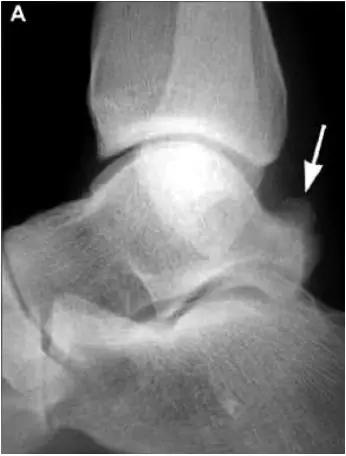

- 踝关节正侧位X 线平片,侧位片均显示距骨后方有三角形或椭圆形的距后三角骨。部分病例伴有轻度的踝关节骨性关节病。

- MRI 检查示距后三角骨及周围软组织有水肿信号,距后三角骨和距骨之间正常的低信号纤维连接中断,出现液性信号。

- 三角籽骨或距骨后三角结构模糊和变形,T1WI信号降低, T2WI信号升高,

- 周围脂肪水肿,

- 踇趾长屈肌腱信号升高,见鞘膜积液,

- 胫骨后下跟骨上缘骨结构形态变化和信号异常,

- 三角籽骨和距骨退行性囊变。